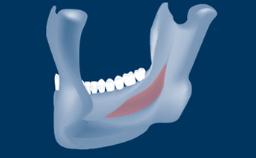

- intraoperative complications of lateral window sinus floor elevation

- intraoperative complications of transcrestal sinus floor elevation

- postoperative complications of sinus floor elevation